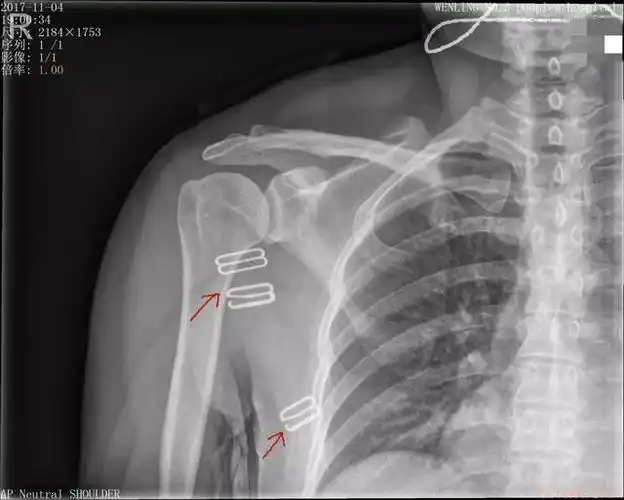

冈上肌钙化性肌腱炎---也许您的"肩周炎"也是这个原因_肩关节损伤_肩

x片示右肩关节冈上肌附着点见多发结节状高密度影,ct扫描示钙化灶,ct